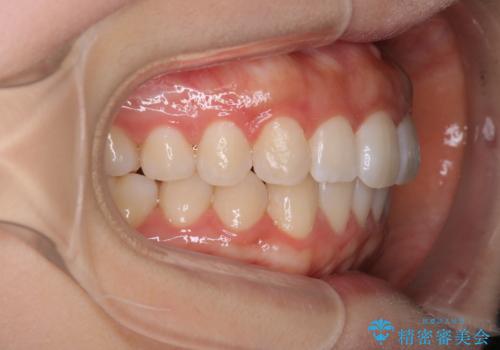

前歯のがたつきをインビザラインで目立たない矯正

- 上下の前歯のがたつきを主訴に来院されました。

マウスピースでの矯正を希望されたので、インビザラインで矯正治療を行うこととしました。

インビザラインではシュミレーションによりどのように歯が動くかを確認して矯正することができるので、患者様も安心して矯正をすることができました。